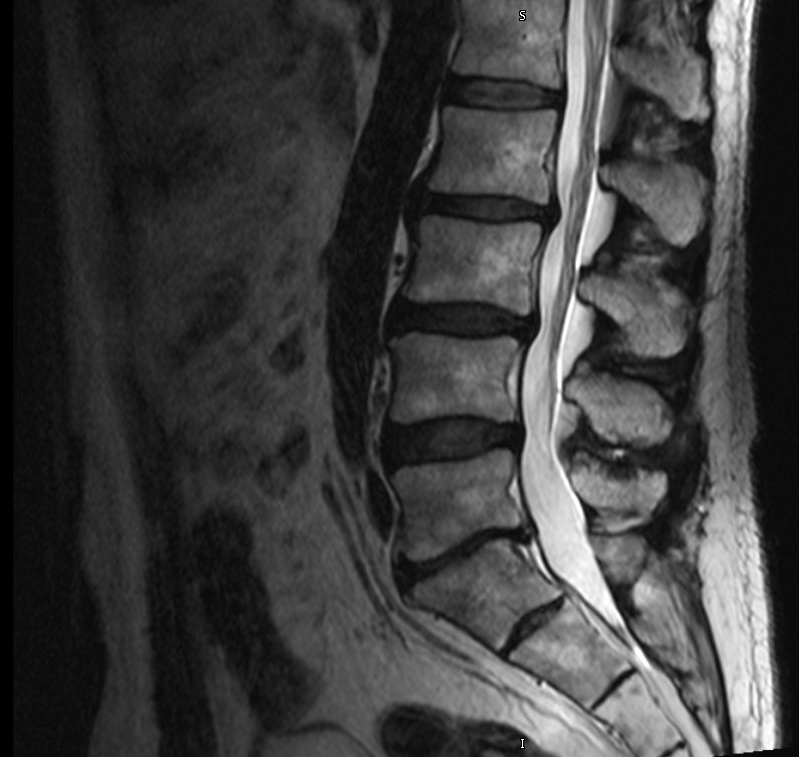

From radiopaedia.org

Lumbar disc arthroplasty Image Unitedhealthcare Lumbar Disc Replacement This change means that millions of patients in. Automated percutaneous lumbar discectomy (apld): Unitedhealthcare issued positive medical policy for lumbar total disc replacement. This leaflet is about when and how artificial discs can be used in the nhs to treat. This decision affects over 16 million patients covered through unitedhealthcare, and means that three out of the four largest us. Unitedhealthcare Lumbar Disc Replacement.